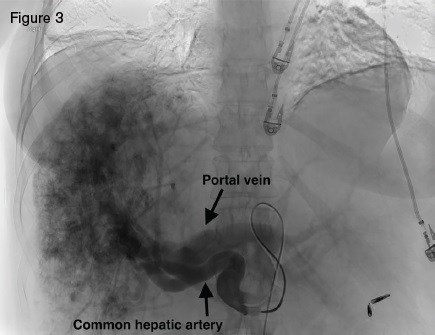

Angiogram displaying large hepatic arteries with shunting primarily from hepatic artery to portal vein.

Angiogram displaying large hepatic arteries with shunting primarily from hepatic artery to portal vein.

A 51-year-old woman with HHT was referred for management of recurrent epistaxis, GI bleeding, iron deficiency anemia, large bilobar hepatic AVMs, and worsening ascites. Gastric AVMs were previously managed with endoscopic argon plasma coagulation. She required regular intravenous iron and occasional blood transfusions to maintain a hemoglobin of seven to 10 g/dL. Elevated liver enzymes two years earlier prompted an ultrasound that demonstrated hepatic AVMs. Magnetic resonance imaging (Figure 2) demonstrated a macronodular liver with diffuse AVMs involving both hepatic lobes, ascites, and splenomegaly. Angiogram demonstrated large hepatic arteries with shunting primarily from hepatic artery to portal vein (Figure 3). She primarily reported weakness, dyspnea on exertion, and worsening ascites requiring weekly six- to seven-L paracentesis.

Hepatic AVMs occur in as many as 74 percent of HHT patients.1 The majority of HHT hepatic AVMs, however, are asymptomatic, making routine screening inadvisable.2 Large hepatic AVMs with extensive arterio-hepatic venous shunting can lead to high-output cardiac failure. When shunting is predominantly between the hepatic artery and portal vein, presinusoidal portal hypertension can develop, leading to ascites and nodular regenerative hyperplasia. Hepatic angiography in our patient demonstrated a large, diffuse, bilobar hepatic AVM with hepatic artery-to-portal vein shunting. The hepatic AVM was thought to be the cause of our patient’s high-output cardiac failure, portal hypertension, and debilitating ascites.